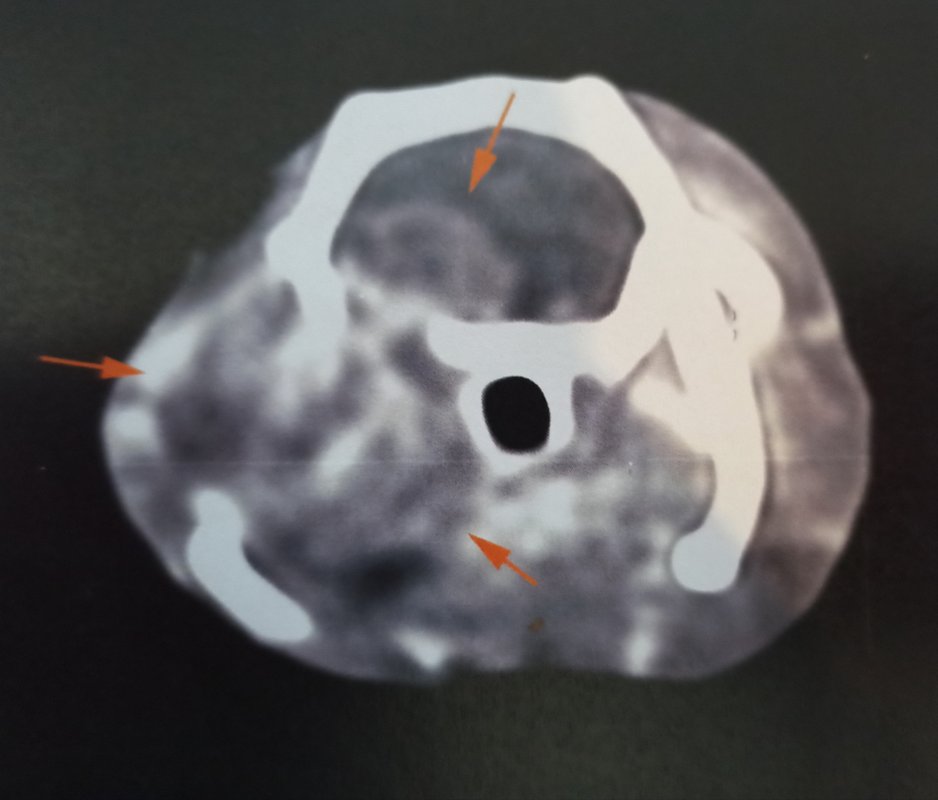

Et effectivement, pour le coup c'était ça. On ne le voit pas de l'extérieur mais il y a un gros gonflement autour de la bulle tympanique, c'est ça qui a décalé sa mâchoire en fait, et malheureusement cela a également atteint le cerveau...

Une chirurgie est possible pour la partie hors du cerveau, ce qui pourrait permettre de le rendre plus confortable pour manger, mais ce n'est pas sans risque d'empirer les choses, et quoi qu'on fasse on n'a pas d'espoir de guérison, seulement de lui faire gagner un peu de temps en gérant au mieux douleur et inconfort. Elle m'a fait une prescription de tramadol à ajouter au reste s'il semble avoir mal.

Je vous partage les images parce que vu le prix qu'elles m'ont coûtées autant que tout le monde en profite ><